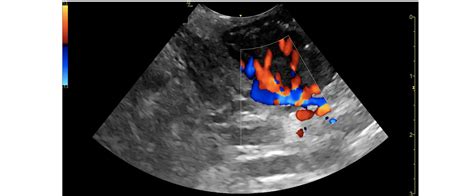

Carotid Ultrasound

A carotid ultrasound uses sound waves to create images of the carotid arteries. This non-invasive procedure helps detect any blockages or narrowing of the arteries, which could indicate the presence of plaque or other issues. The ultrasound provides valuable information for planning further interventions, including Carotid Artery Shots.